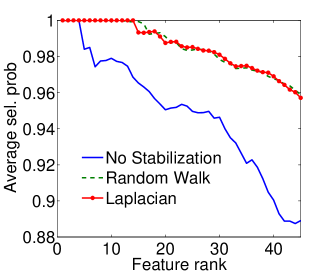

|

|

| (a) Cumulative, | (b) Stagewise (Shared), |

|

|

| (c) Stagewise (Separate), | (d) Stagewise (Separate), |

We now examine the models stability against data sampling and evaluate the stabilizing property of the proposed method (Sec. 6.2). For each fold, we generated samples, each of which was drawn randomly from % of training data. Each example resulted in a model, and the feature weights were recorded and finally the results of all folds – models – were combined. Figs. 5(a–d) show the indices (Eq. (5)) as functions of the rank list size , for all ordinal classifiers. The instability is clearly an issue – the average selected probability drops as more features are included. Using both the Laplacian and random walk regularization methods (Eqs. (9,10)), the improvement in stability is evidenced in all settings. The instability and stabilizing effect were similarly obtained with the indices (Figs. 6(a–d)).

|

|

| (a) Cumulative, | (b) Stagewise (Shared), |

|

|

| (c) Stagewise (Separate), | (d) Stagewise (Separate), |